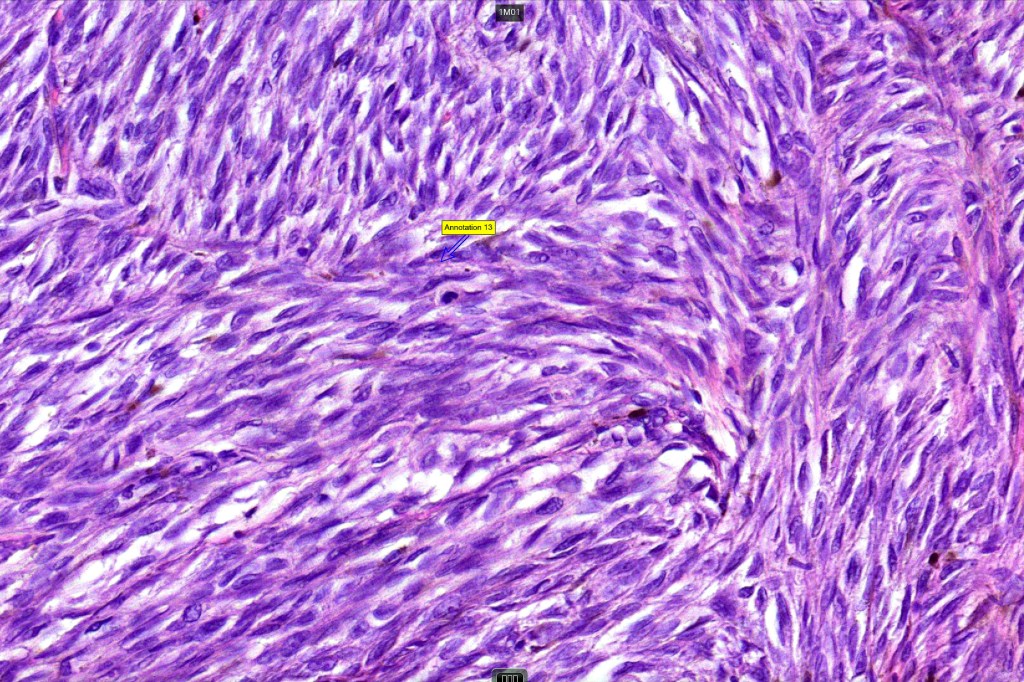

Histological features

•Develops within a precursor lesion as one or more nodules of epithelioid or spindled cell melanoma

•Nuclear pleomorphism with prominent nucleoli, mitotic activity & abnormal mitoses